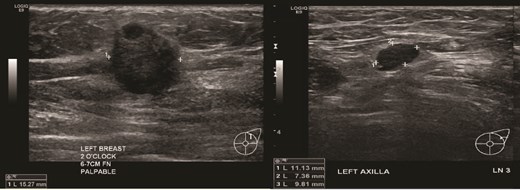

(Left) Ultrasound image of the left breast hypoechoic lesion; (Right) Ultrasound image of one of several enlarged lymph nodes with effacement of fatty hilum.

Patient C, aged 70, had no significant past medical history and initially presented to Otolaryngology with right-sided cervical lymphadenopathy. Excision biopsy confirmed a diagnosis of diffuse large B cell lymphoma (DLBCL). She then reported a 3-month history of a left breast lump. Clinical examination and imaging revealed a 20 mm lesion associated with ipsilateral axillary lymphadenopathy (Figs 7 and 8). Triple assessment confirmed triple negative invasive ductal carcinoma in the breast, whilst there were follicular cells in the nodes (Fig. 9). She underwent systemic chemotherapy for stage III diffuse large B-cell lymphoma using Rituximab, cyclophosphamide, doxorubicin, vincristine, and prednisolone (R-CHOP) protocol followed by weekly Paclitaxel for the concurrent breast cancer. She achieved clinical remission for lymphoma. Subsequently she underwent breast conserving surgery with sentinel node biopsy, and adjuvant chest radiotherapy.